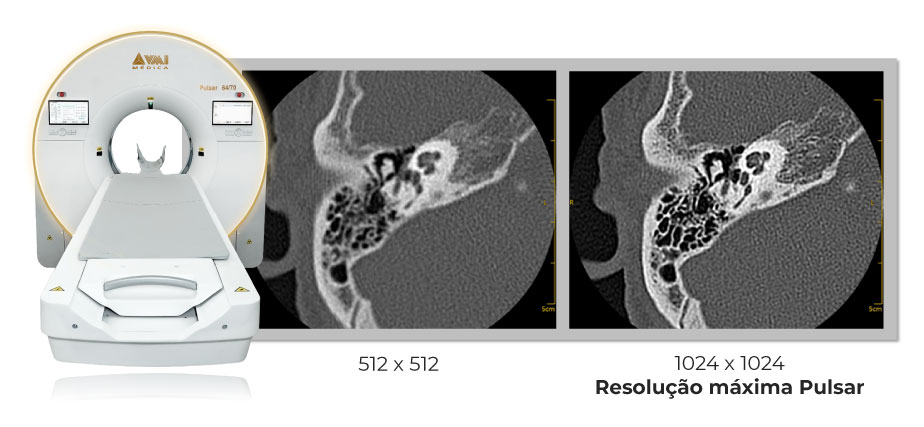

A linha Pulsar de tomografia computadorizada redefine a tecnologia no diagnóstico por imagem ao combinar inteligência artificial e engenharia de precisão.

Imagens mais nítidas

Alta performance para cenários que exigem máxima definição e produtividade. O Pulsar 128 une tecnologia avançada, velocidade de aquisição e excelência em imagem, com opções de abertura que ampliam o conforto e tornam o exame mais acessível a diferentes perfis de pacientes.